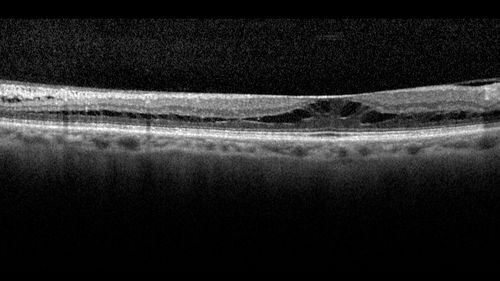

Stellate Non-heredtiary Idiopathic Foveomacular Retinoschisis (SNIFR)

77 year old man who is healthy and 6'6" tall with 20/40 vision and no complaints. OCT shows diffuse retinoschisis.